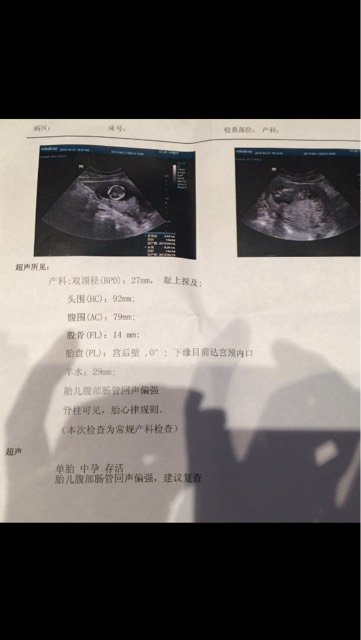

怀孕13加6今天去医院建卡常规BC检查结果其它都好,就是胎儿腹部肠管回声偏强,建议复查,抽血化验单

怀孕13加6今天去医院建卡常规BC检查结果其它都好,就是胎儿腹部肠管回声偏强,建议复查,抽血化验单没拿全今天也就没去找医生,回来网上查了下说的蛮严重的,好担心,希望我的宝宝没事,有没知道这种情况的宝妈医生给点建议,好担心~

建议做个羊水穿刺,结果是好的,医生说后头随诊复查就行,保持乐观心态吧,孩子肯定没事,B超说明不了什么。